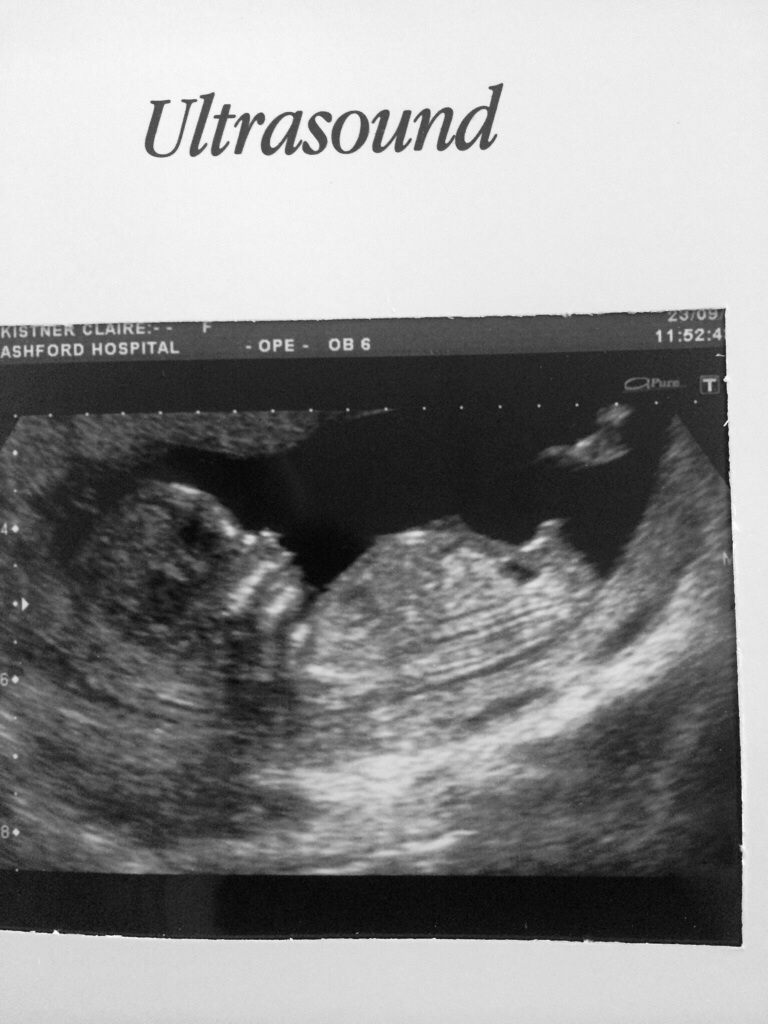

So I am going to upload a picture of my 12 week scan (was actually measuring 13+2) as I am trying to work out if what I am seeing is a nub (in which case I am thinking we are having a second boy) or part of its leg?? I am useless at this! I think I can see about three different nubs, all of which look different!!

I would love to get some more experienced eyes to look over it and give me a guess on whether you think Boy or Girl!! Also if you could highlight or tell me what the nub is in the picture that would be awesome!!

Absolutely classic boy nub. She ^^ circled it perfectly. I don't know what is floating up there. It looks like possibly a blurry cord image. Or it could just be "noise" in the sonogram and not a part at all. Potentially a foot. But, it's not connected to the nub, which is very clear.

What Tx circled is the nub. It's not floating. It's what is referred to as a "stacked" nub. The genital tuber had begun angling upward to form a penis and scrotum. There is no fork. A fork is fairly obvious like this: --< when imaged on a nub. And a fork is not indicative of gender at all, it's just a shape of nubs. A straight angled nub, directly out from the body is a girl nub. A nub angled upward toward the sky or back to toward baby's head is indicative of a boy.

I circled the entire nub area, the part sticking up an obvious boy part. With just the one picture it can be hard to tell what everything is, but I would be really surprised if this is not a boy :) The floaty thing could be cord, could be leg as you suspect...I cannot tell though. Cute little baby though!